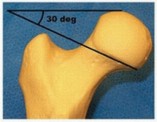

DEFINITION Femoral neck fractures occur in two patient populations. Most commonly, they happen in older osteopenic patients after low-energy trauma, such as falls. When they occur in younger patients with normal bone, they are usually the result of high-energy trauma, such as a motor vehicle collision. Femoral neck fractures can be classified by several characteristics. The most important distinguishing feature in regard to treatment decisions is the degree of displacement. Fractures that are nondisplaced or impacted into valgus can usually be treated with fixation in situ using percutaneous methods. Displaced fractures usually require reduction and fixation or replacement. The location of the fracture in the femoral neck can be described as subcapital, transcervical, or basicervical ( FIG 1). Transcervical femoral neck fractures can be further characterized by the angle of the fracture line with respect to the perpendicular of the femoral shaft axis. This is the Pauwels classification ( Table 1). The importance of this feature is to recognize highangle fractures (more vertical), which have the greater risk of displacement when treated with screws along the neck axis. ### FIG 1 • Definition of location for femoral neck fractures. Fractures through the red zone are described as basicervical; in the yellow zone , they are transcervical; and in the green area , they are designated subcapital.

Fixation Pauwels 1 Low, ≤30 degrees Compression, stable Lag screws in axis of femoral neck Pauwels 2 30-50 degrees Variable Lag screws in axis of femoral neck Pauwels 3 High, ≥50 degrees Shear, unstable; tends to displace into shortened, varus position At least one lag screw perpendicular to fracture plane